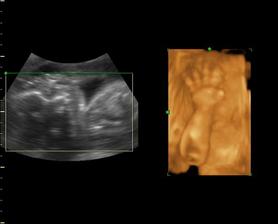

My a náš prvý očakávaný anjelik

Po roku dlhého skúšania sa nám konečne podarilo...Sme s manželom veľmi šťastní a nevieme sa našeho prvo-rodeného bábatka dočkať.